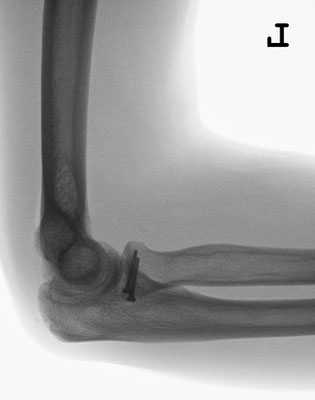

Radiusköpfchenbruch/Speichenköpfchenbruch

Einfache, sog. „Meißelbrüche“ des Speichenköpfchens können durch Minischrauben sehr stabil fixiert werden. Komplizierte Brüche müssen event. mit Miniplättchen verschraubt werden.

Bei ausgedehnter Zertrümmerung des Radiusköpfchens kann dieses mit Miniplättchen rekonstruiert werden oder sogar vollständig entfernt werden, ohne das die Funktion des Ellenbogens stark beeinträchtigt wird.

Häufiger kommt es allerdings zu zusätzlichen Bandverletzungen, insbesondere wenn der Ellenbogen luxiert war. In diesem Fall muss das Radiusköpfchen unbedingt erhalten werden, oder durch eine Radiusköpfchenprothese ersetzt werden. Durch die Wiederherstellung der knöchernen Führung wird die Stabilität des Ellenbogengelenkes wieder hergestellt. Zusätzlich wird der Bandapparat während der Operation genäht.